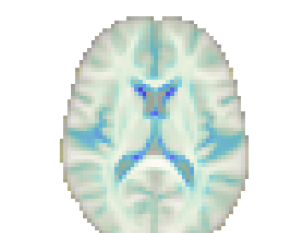

A key advantage of the proposed method over discriminative methods such as RVoxM and SFCN is that, in addition to the discriminative map that it uses to make predictions, it also computes a generative map that expresses the causal effect of the variable of interest on brain morphology. To illustrate why this is important, Fig. 9 shows, for three different training set sizes, the discriminative map computed by our method for predicting age, along with the corresponding discriminative map of RVoXM and the SmoothGrad saliency map (Smilkov et al., 2017) – a generalization of linear spatial maps to nonlinear methods (Adebayo et al., 2018) – of SFCN. The inconsistencies of these maps across both the training set sizes and the different methods, and their overall lack of correspondence with the known neurobiology of aging, illustrate the difficulty of using discriminative maps for human interpretation.

More insight can be gained by examining the proposed method specifically, since it uses disciminative maps that are derived from generative ones. It is worth noting that estimating the generative maps from training data is itself quite stable, since it merely amounts to fitting two basis functions to hundreds of measurements in each voxel (cf. (8)). Furthermore, as illustrated in Fig. 10, the resulting maps are intuitive to interpret, since they show typical age-related effects such as cortical thinning and ventricle enlargement (Fjell et al., 2009; Fjell and Walhovd, 2010). When the discriminative maps are subsequently computed as , however, a strong dependency on the training set size is introduced, because the method explicitly controls the complexity of its noise model in response to the size of the available training set (the bias-variance trade-off of Sec. 4.4). can also capture peculiarities in the data that may be relevant for improving prediction performance, but not for human interpretation. An example of this was shown in Fig. 5, where overall brightness variations and residual MR bias field artifacts were picked up by the noise model. Through , such noise patterns can find their way into , producing hard-to-interpret spatial maps that no longer reflect the expected age-related brain atrophy patterns. This is clearly illustrated in Fig. 4, where the discriminative map is contrasted with the corresponding generative map .